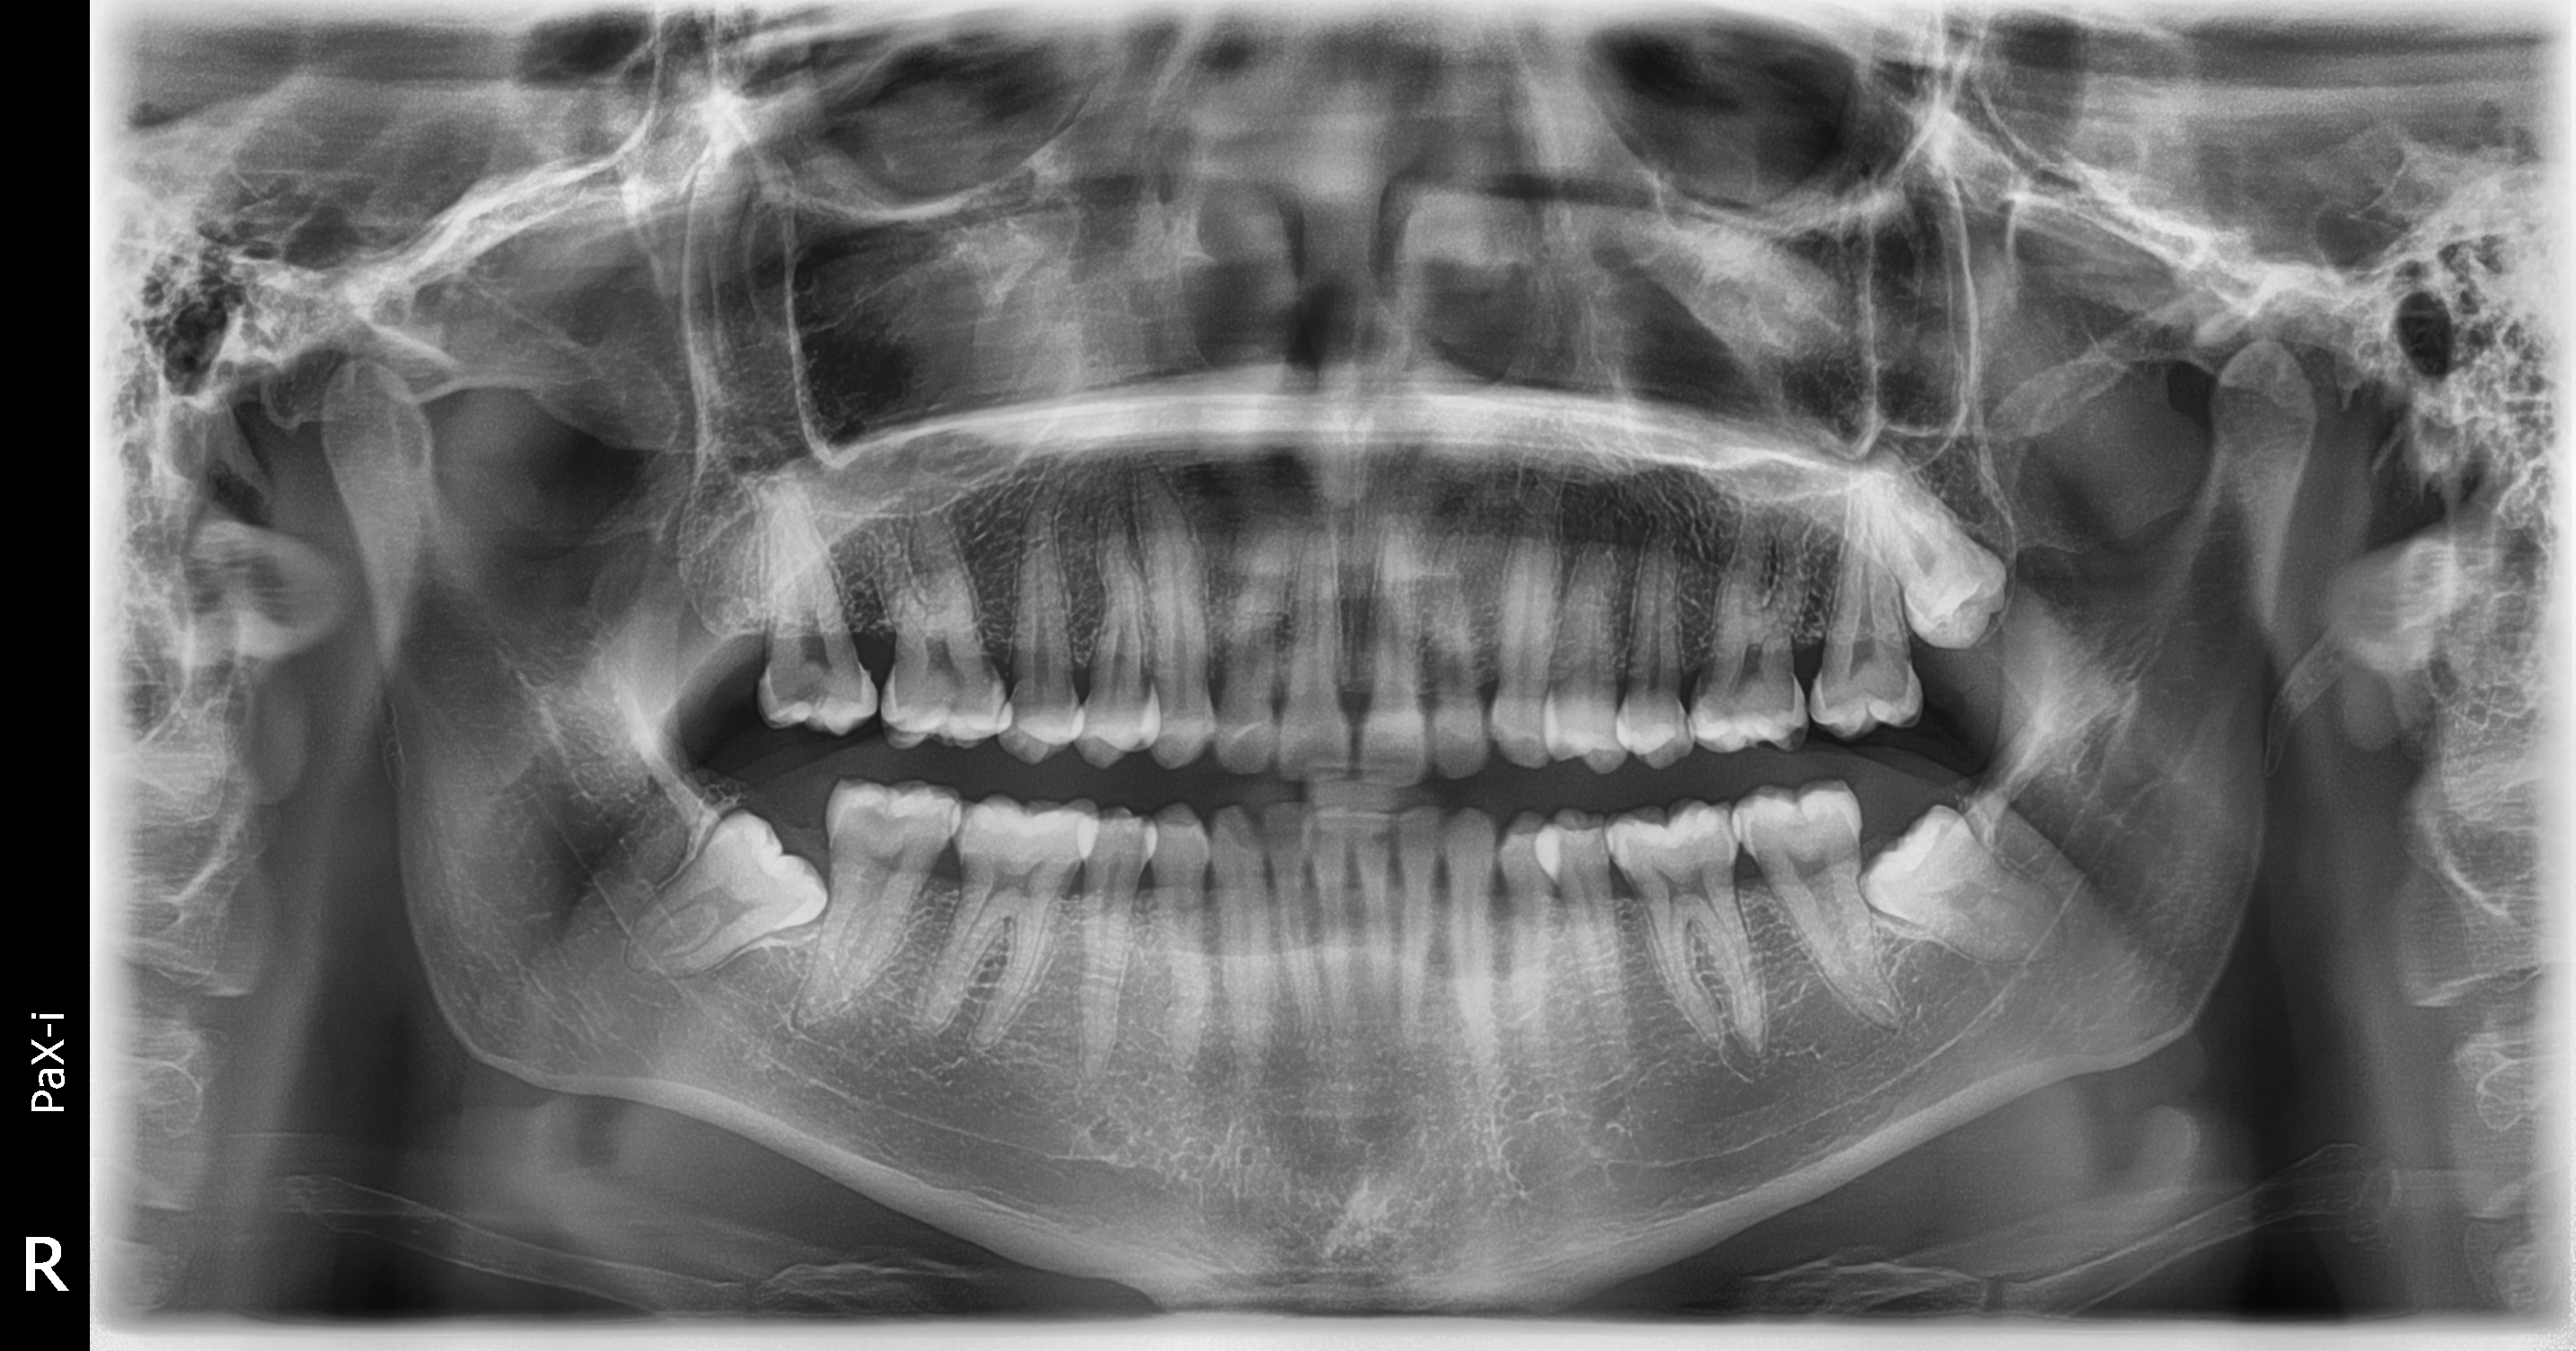

Gracias al Dr. Fernando Peña , por seguir confiando en nosotros y adquirir su nuevo equipo. Centro ubicado en Villa el Salvador - Lima, instalación de equipo PaX-i SC (Panorámico/Cefalometrico) de la marca VATECH.